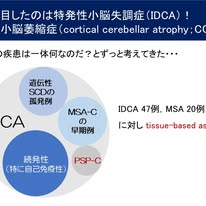

まず第1のパートでは,特発性小脳失調症(IDCA/CCA)における自己免疫の関与について取り上げました.IDCAでは約34%と高頻度に意義不明ながら抗小脳抗体が検出されることを見いだしました.特に小脳血流の左右差を認める症例では,免疫学的機序の関与が疑われ,抗体測定が必要と考えています.現在,ステロイドパルス療法の有効性を検証する医師主導治験を進めています.もしIDCA/CCA患者さんがいらっしゃったらTissue-based assayによる抗体検索をさせていただければありがたいです.

■ とくに特発性小脳失調症(IDCA,かつてのCCA)では注意が必要;約3割で抗小脳抗体が陽性

私たちはまず,IDCAに着目しました.さまざまな病態が含まれている可能性がありますが,その中に自己免疫性のACAが含まれているという仮説を立てました(図1).IDCA,多系統萎縮症(MSA-C),遺伝性脊髄小脳失調症,健常者を対象にtissue-based assay(TBA)を行ったところ,IDCA群の34%(47例中16例)で抗小脳抗体が陽性となり,他群と比べて明らかに高頻度でした.この結果は,IDCAの中に自己免疫性病態が含まれている可能性を示唆します(図2,3).